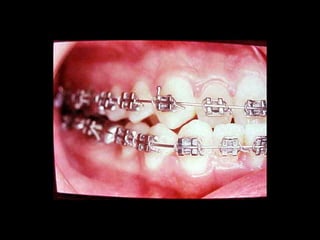

La paciente fue manejada iatrogénicamente por 5 años

Utilizando diferentes implementos ortodóncicos

La regla es clara: Laterognatias de más de 2º son quirúrgicas

La paciente fuemanejada iatrogénicamente por 5 años Utilizando diferentes implementos ortodóncicos La regla es clara: Laterognatias de más de 2º son quirúrgicas

La paciente muestrauna franca disgnatia, clínicamente observamos malposición dentaria secundaria a la falta de armonía máxilomandibular. La paciente muestra una franca disgnatia, clínicamente observamos malposición dentaria secundaria a la falta de armonía máxilomandibular.

Marcada Clase III HábitoLingual Marcada Clase III Hábito Lingual Sobremordida horizontal: –1.5 mm Sobremordida vertical: + 1 mm. Sobremordida horizontal: –1.5 mm Sobremordida vertical: + 1 mm.